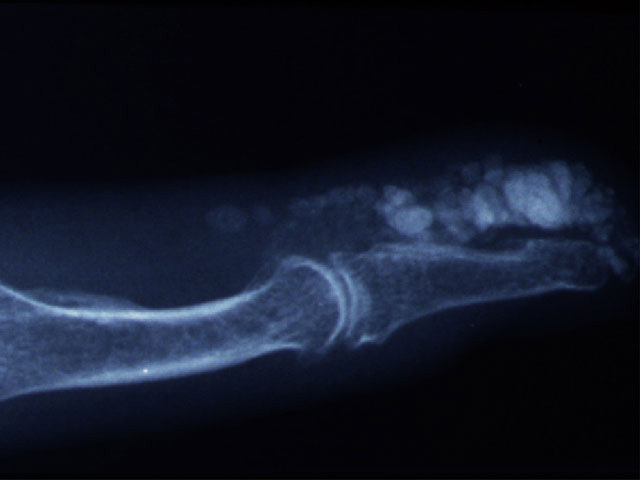

Digital calcinosis

X-ray of calcinosis